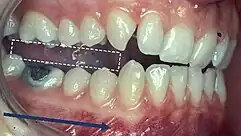

Non-working side interference (photograph) detectable with articulating paper or plastic shimstock, as the mandible moves to the left (working side). (Institute of Dentistry Aberdeen University)

The occlusal interferences may be classified as follows:[22]

1. Working Side Interference: When there is a heavy or early tooth contact between the maxillary and mandibular teeth on the side that the mandible is moving towards, and this contact may or may not discludes the anteriors.[18]

2. Non-Working Side Interference: An occlusal contact on the side the mandible is moving away from that prevents harmonious movement of the mandible. These have the potential to be more destructive in comparison to WS interferences due to the obliquely directed forces.[23]